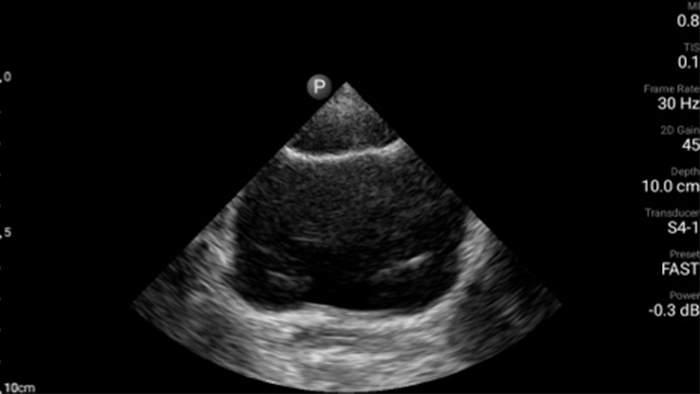

Exceptional ultrasound imaging

Lumify handheld ultrasound offers images that enhance diagnostic confidence.